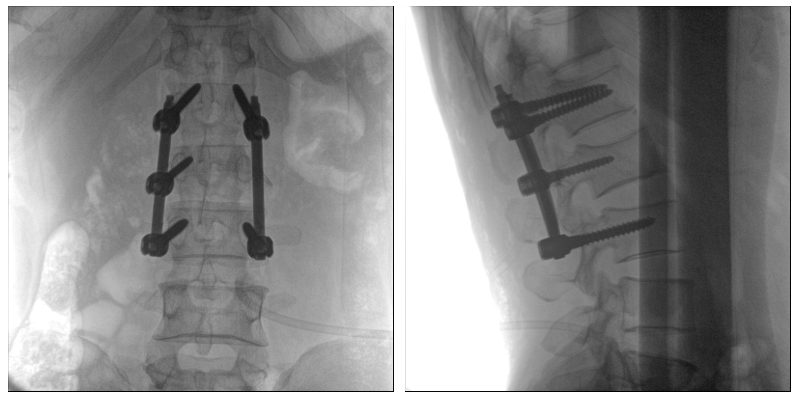

為手術保駕護航

術中三維C臂影像帶來的更加豐富的信息,可以作為醫生手術執行的判斷基礎,以及手術操作后實時的影像判斷依據,從而保障手術效果。

在既往的手術中可能會出現這樣的情況:術后在影像科CT檢查中發現某個手術效果需要調整,這時往往需要返臺、翻修等才能解決。而術中三維C臂提供的術中三維影像功能可以將這一步驟合并至手術流程中,有效地降低醫患雙方的風險,為手術保駕護航。

機器人導航的影像基礎

近年來,機器人導航設備在臨床的應用越來越廣泛,而術中三維C臂影像是機器人導航系統手術執行的基礎,具有地圖定位和效果檢驗的雙重作用,使手術執行更加準確,手術效果驗證更有保障。